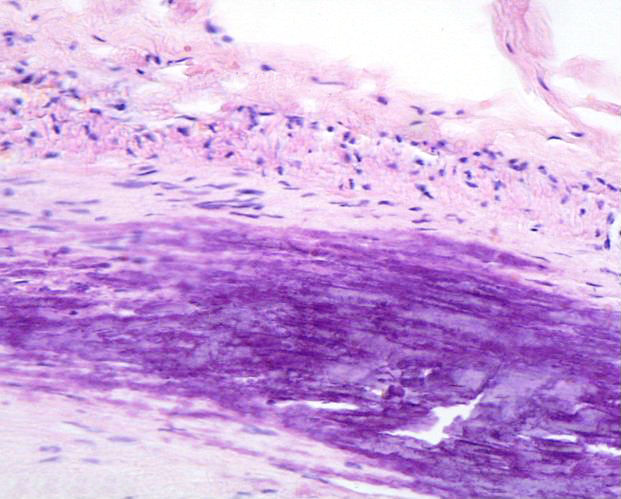

Aterosklerotiese plaak

Atherosclerotic plaque